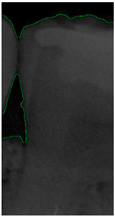

Figure 8.

Image-enhancement results: (a) binarization; (b) mathematical morphology; (c) added green line represents canny; (d) overlap onto the original image.

2.3.5. Canny Edge Detection

Since filtered and binarized images alone cannot enhance the features of dental calculus, this approach does not effectively improve the accuracy of machine learning. Therefore, this study employed edge detection to identify the contours of tooth edges, enhancing the regions of interest and thereby improving the accuracy of machine learning. The canny edge-detection algorithm applies non-maximum suppression to each pixel, retaining pixels with local maximum gradient values, which can produce continuous and accurate edges while demonstrating good resistance to noise. The edge-detection results are represented in green, as shown in Figure 8c. Finally, these results are overlaid back onto the original image, as illustrated in Figure 8d.